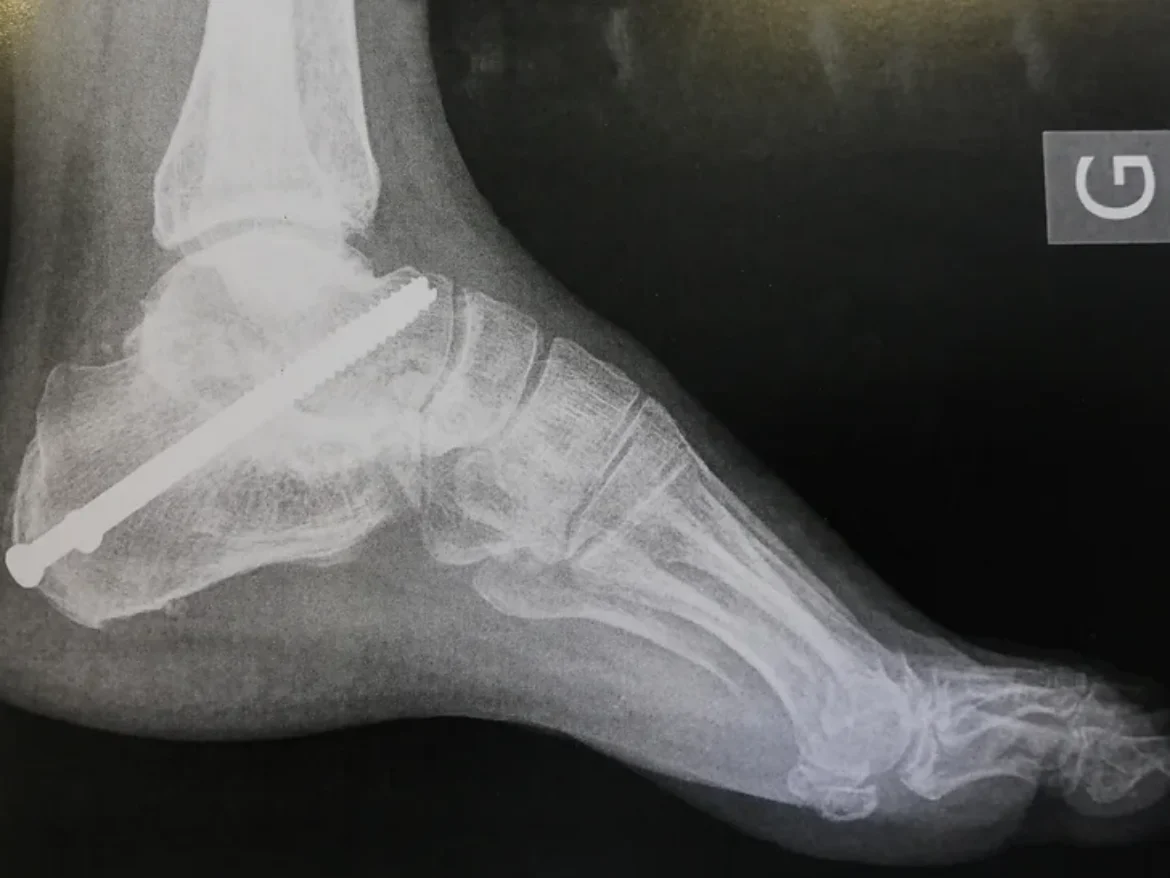

Des interventions de pointe sur la hanche, le genou, la cheville, le pied, l’épaule, la main & le poignet, permettent de rétablir ou d’améliorer leur mouvement et leur fonction.

En combinant savoir-faire chirurgical et technologies innovantes, le Dr Majed Issa intervient sur de nombreuses pathologies articulaires. Que ce soit pour une arthroscopie de la hanche, une prothèse de genou personnalisée, ou encore une intervention sur l’épaule, le pied, la cheville, la main ou le poignet, nous mettons en œuvre des techniques précises et adaptées à chaque patient.